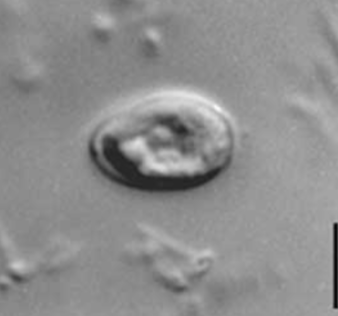

Cryptospordium

Cryptosporidum

Cyclospora cayetanensis